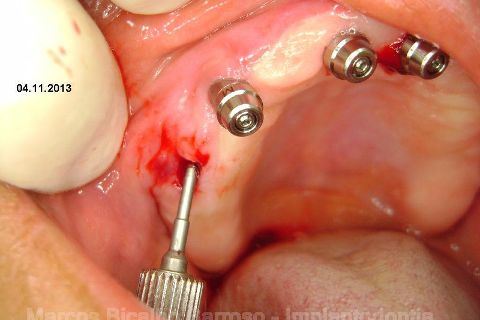

Atualização do caso clínico que já postei, "REABILITAÇÃO EM MAXILA ATRÓFICA COM IMPLANTES", um caso que inclui expansão do rebordo estreito com cinzel e martelo, expansores rosqueáveis, enxerto e instalação dos implantes distais inclinados tangenciando seio maxilar. Inclui esvaziamento do forame nasopalatino e preenchimento com biomaterial para instalação de dois implantes próximos dele. Cirurgia realizada em única sessão, com instalação dos 6 implantes. Para os colegas que não conheceram e/ou esqueceram da apresentação, este é o resumo do caso na fase cirúrgica.http://www.youtube.com/watch?v=BtvexFexRPA&hd=1

FASE PROTÉTICA DA REABILITAÇÃO EM MAXILA ATRÓFICA...incluindo a reabertura, instalação dos minipilares e PTR provisória reembasada sobre os cilindros de proteção.